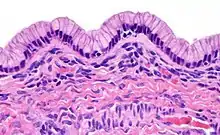

| Surface epithelial-stromal tumor | Serous tumor | 25% | 18.5% | Benign serous tumors of the right ovarian cyst are thinwalled unilocular cysts that are lined by ciliated pseudostratified cuboidal or columnar epithelium.[6] |  |